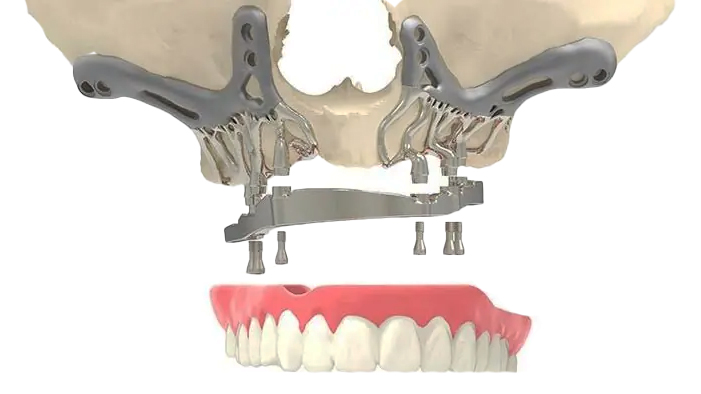

Zygomatic Dental Implants

Zygomatic implants are a type of dental implant specifically designed for patients with severe bone loss in the upper jaw. Unlike traditional implants that are anchored into the jawbone, zygomatic implants are longer and are anchored into the zygoma, or cheekbone. This provides a stable and robust foundation for dental prosthetics, even in cases where the upper jawbone is insufficient to support conventional implants.

Zygomatic implants can often be placed without the need for bone grafting, making them a quicker and less invasive solution for patients with significant bone loss. This innovative approach allows for full-mouth rehabilitation, restoring function and aesthetics for individuals who might otherwise be unable to receive dental implants.

Subperiosteal Dental Implants

Subperiosteal dental implants are a type of implant that rests on top of the jawbone but beneath the gum tissue. Unlike traditional implants that are inserted into the bone, subperiosteal implants consist of a custom-made metal framework that is designed to fit perfectly over the bone. This framework has posts that protrude through the gum to support the dental prosthesis.

The introduction of subperiosteal implants marks a significant advancement in the field of implant dentistry, offering a solution that is less invasive than traditional methods yet equally robust. The innovative design and custom fabrication process encompass the most advanced technology to ensure a precise fit and optimal results.

Zygomatic Dental Implants

Zygomatic implants are a type of dental implant specifically designed for patients with severe bone loss in the upper jaw. Unlike traditional implants that are anchored into the jawbone, zygomatic implants are longer and are anchored into the zygoma, or cheekbone. This provides a stable and robust foundation for dental prosthetics, even in cases where the upper jawbone is insufficient to support conventional implants.

Zygomatic implants can often be placed without the need for bone grafting, making them a quicker and less invasive solution for patients with significant bone loss. This innovative approach allows for full-mouth rehabilitation, restoring function and aesthetics for individuals who might otherwise be unable to receive dental implants.

Subperiosteal Dental Implants

Subperiosteal dental implants are a type of implant that rests on top of the jawbone but beneath the gum tissue. Unlike traditional implants that are inserted into the bone, subperiosteal implants consist of a custom-made metal framework that is designed to fit perfectly over the bone. This framework has posts that protrude through the gum to support the dental prosthesis.

The introduction of subperiosteal implants marks a significant advancement in the field of implant dentistry, offering a solution that is less invasive than traditional methods yet equally robust. The innovative design and custom fabrication process encompass the most advanced technology to ensure a precise fit and optimal results.